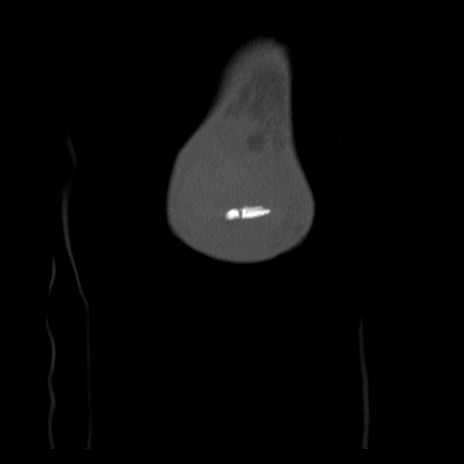

横断像